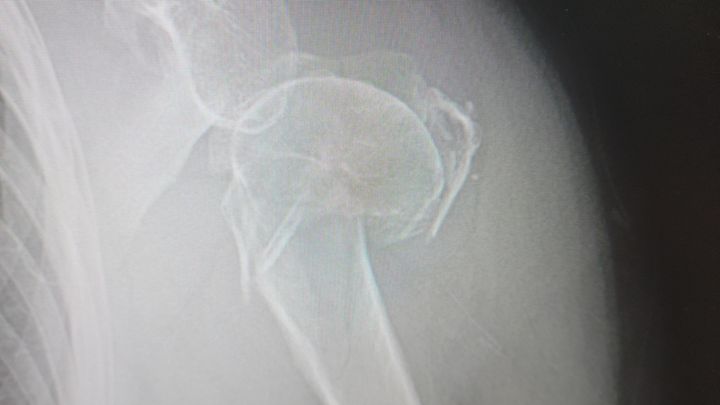

I never imagined I'd be in a position to ask for help like this, but right now I truly need it. As you well know, life has a way of throwing the unexpected at us. Tuesday was that day for me. I fell at home. My left shoulder is broken in three places and cannot be repaired. An injury that has turned everyday tasks into painful challenges. Urgent care confirmed the break Wednesday and referred me to an Orthopedic Surgeon. Yesterday, the Ortho confirmed the severity of the fractures and recommends a shoulder replacement. As I write this, I have no use of my left arm and severe pain.

Complicating things, 13 years of primary caregiving, funeral expenses for both parents, my own early retirement due to back and hip issues, and another fall in 2023 in which I fractured my wrist (I am currently awaiting disability determination by SSA and unable to work) and resulted in plates and eight screws being inserted have all overwhelmed our limited resources and savings. I was just going to begin trying to work again part-time as the SSA determination may take another 5 months. We simply need help with the advance payment.